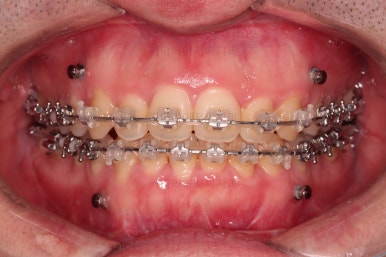

부산긴얼굴긴턱교정 전후 비교해 볼게요.

이렇게 비교해 놓으니 더 드라마틱하죠.

당연히 교합/위아래 폭 등 치열이 좋아졌고요.

얼굴 모습에서도 주걱턱이 개선되었고, 긴얼굴, 긴턱 등 길이 부분도 굉장히 좋아졌습니다.

적절한 협진을 통해서 과하지 않게 특유의 양악수술 느낌의 어색함 없이 개선이 잘 되었습니다.

얼굴 길이가 짧아지면 이렇게 훨씬 어려보이는 효과도 주게 됩니다.

전반적으로 부산긴얼굴긴턱교정 키다리아저씨치과도 환자분도 매우 만족한 치료였습니다.